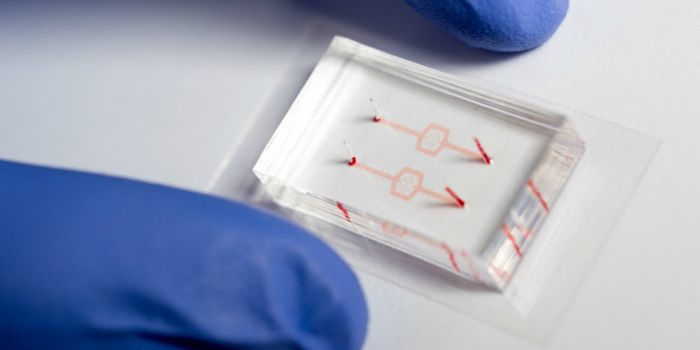

OCT 05, 2016CardiologyScientists reach roadblocks when they try to study diseases of the human heart merely because of its necessity for human ...

MAR 31, 2015CardiologyA team of investigators at Children's Hospital Los Angeles (CHLA) and the University of Southern California have develop ...